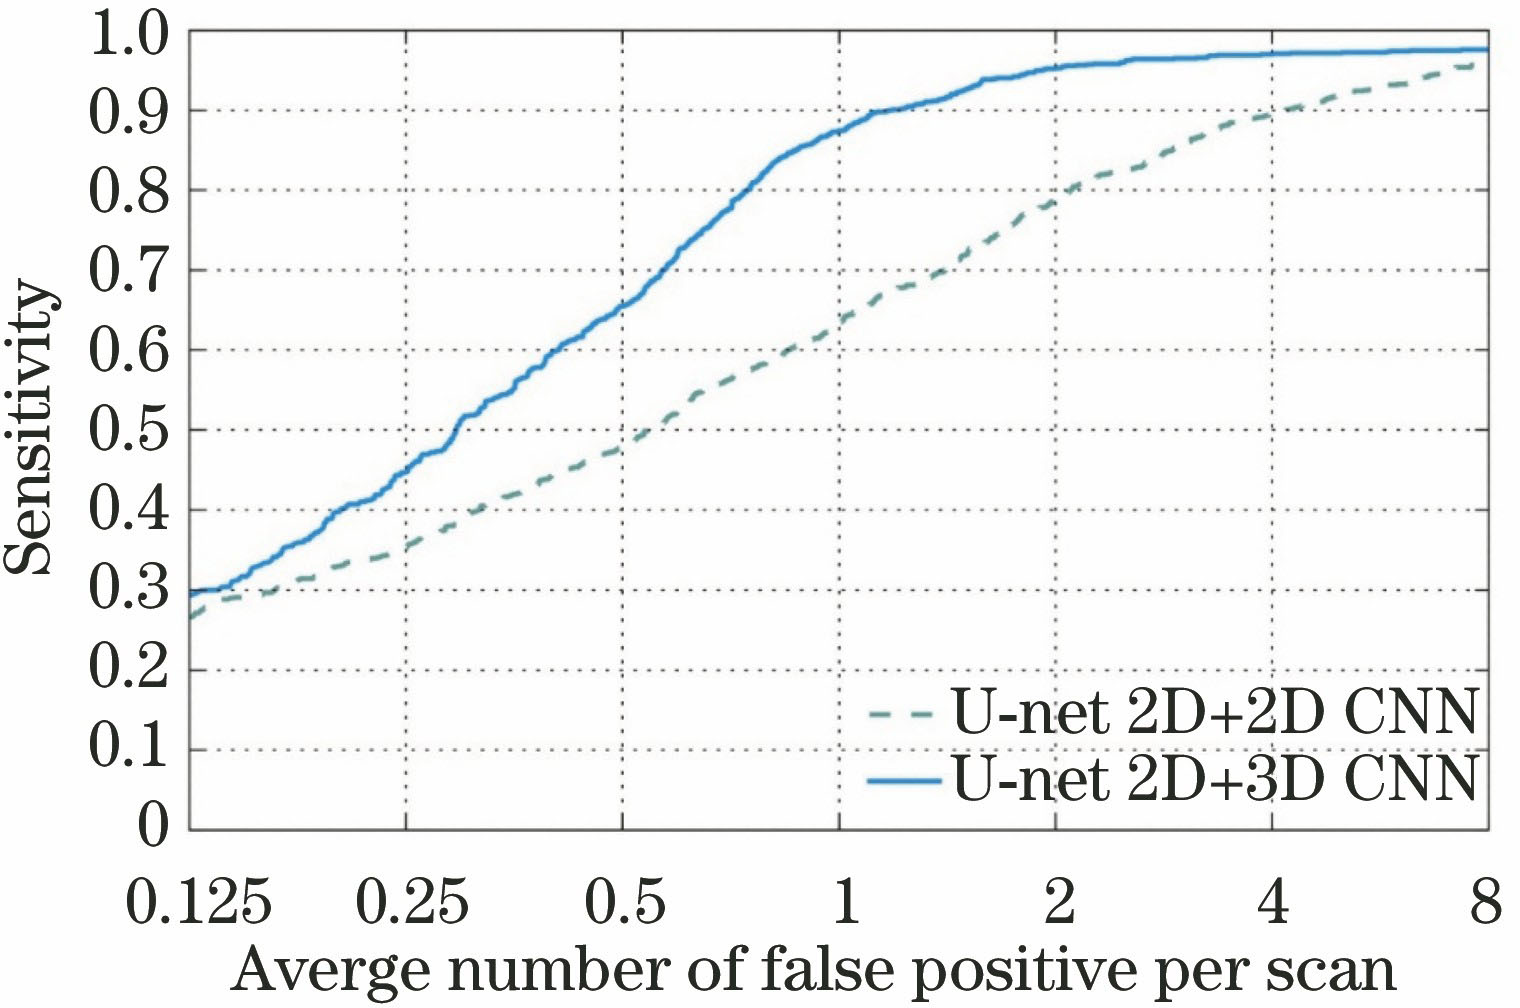

图 9. 网络模型的选择对实验结果的影响

Fig. 9. Effect of the selection of network model on experimental results